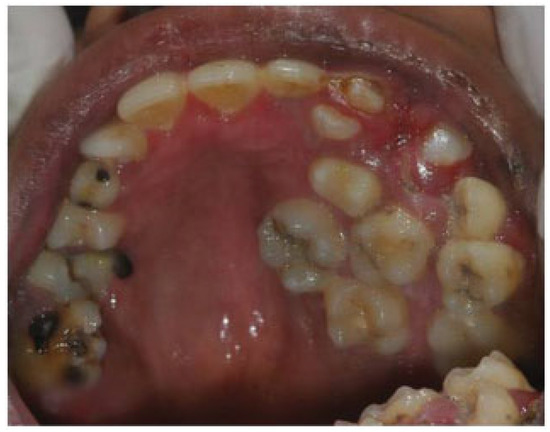

- Incomplete Tessier 7 soft tissue facial cleft and a complete skeletal Tessier 7 cleft on the right side

- Incomplete Tessier 5 skeletal and soft tissue Tessier 6 facial cleft on the left side